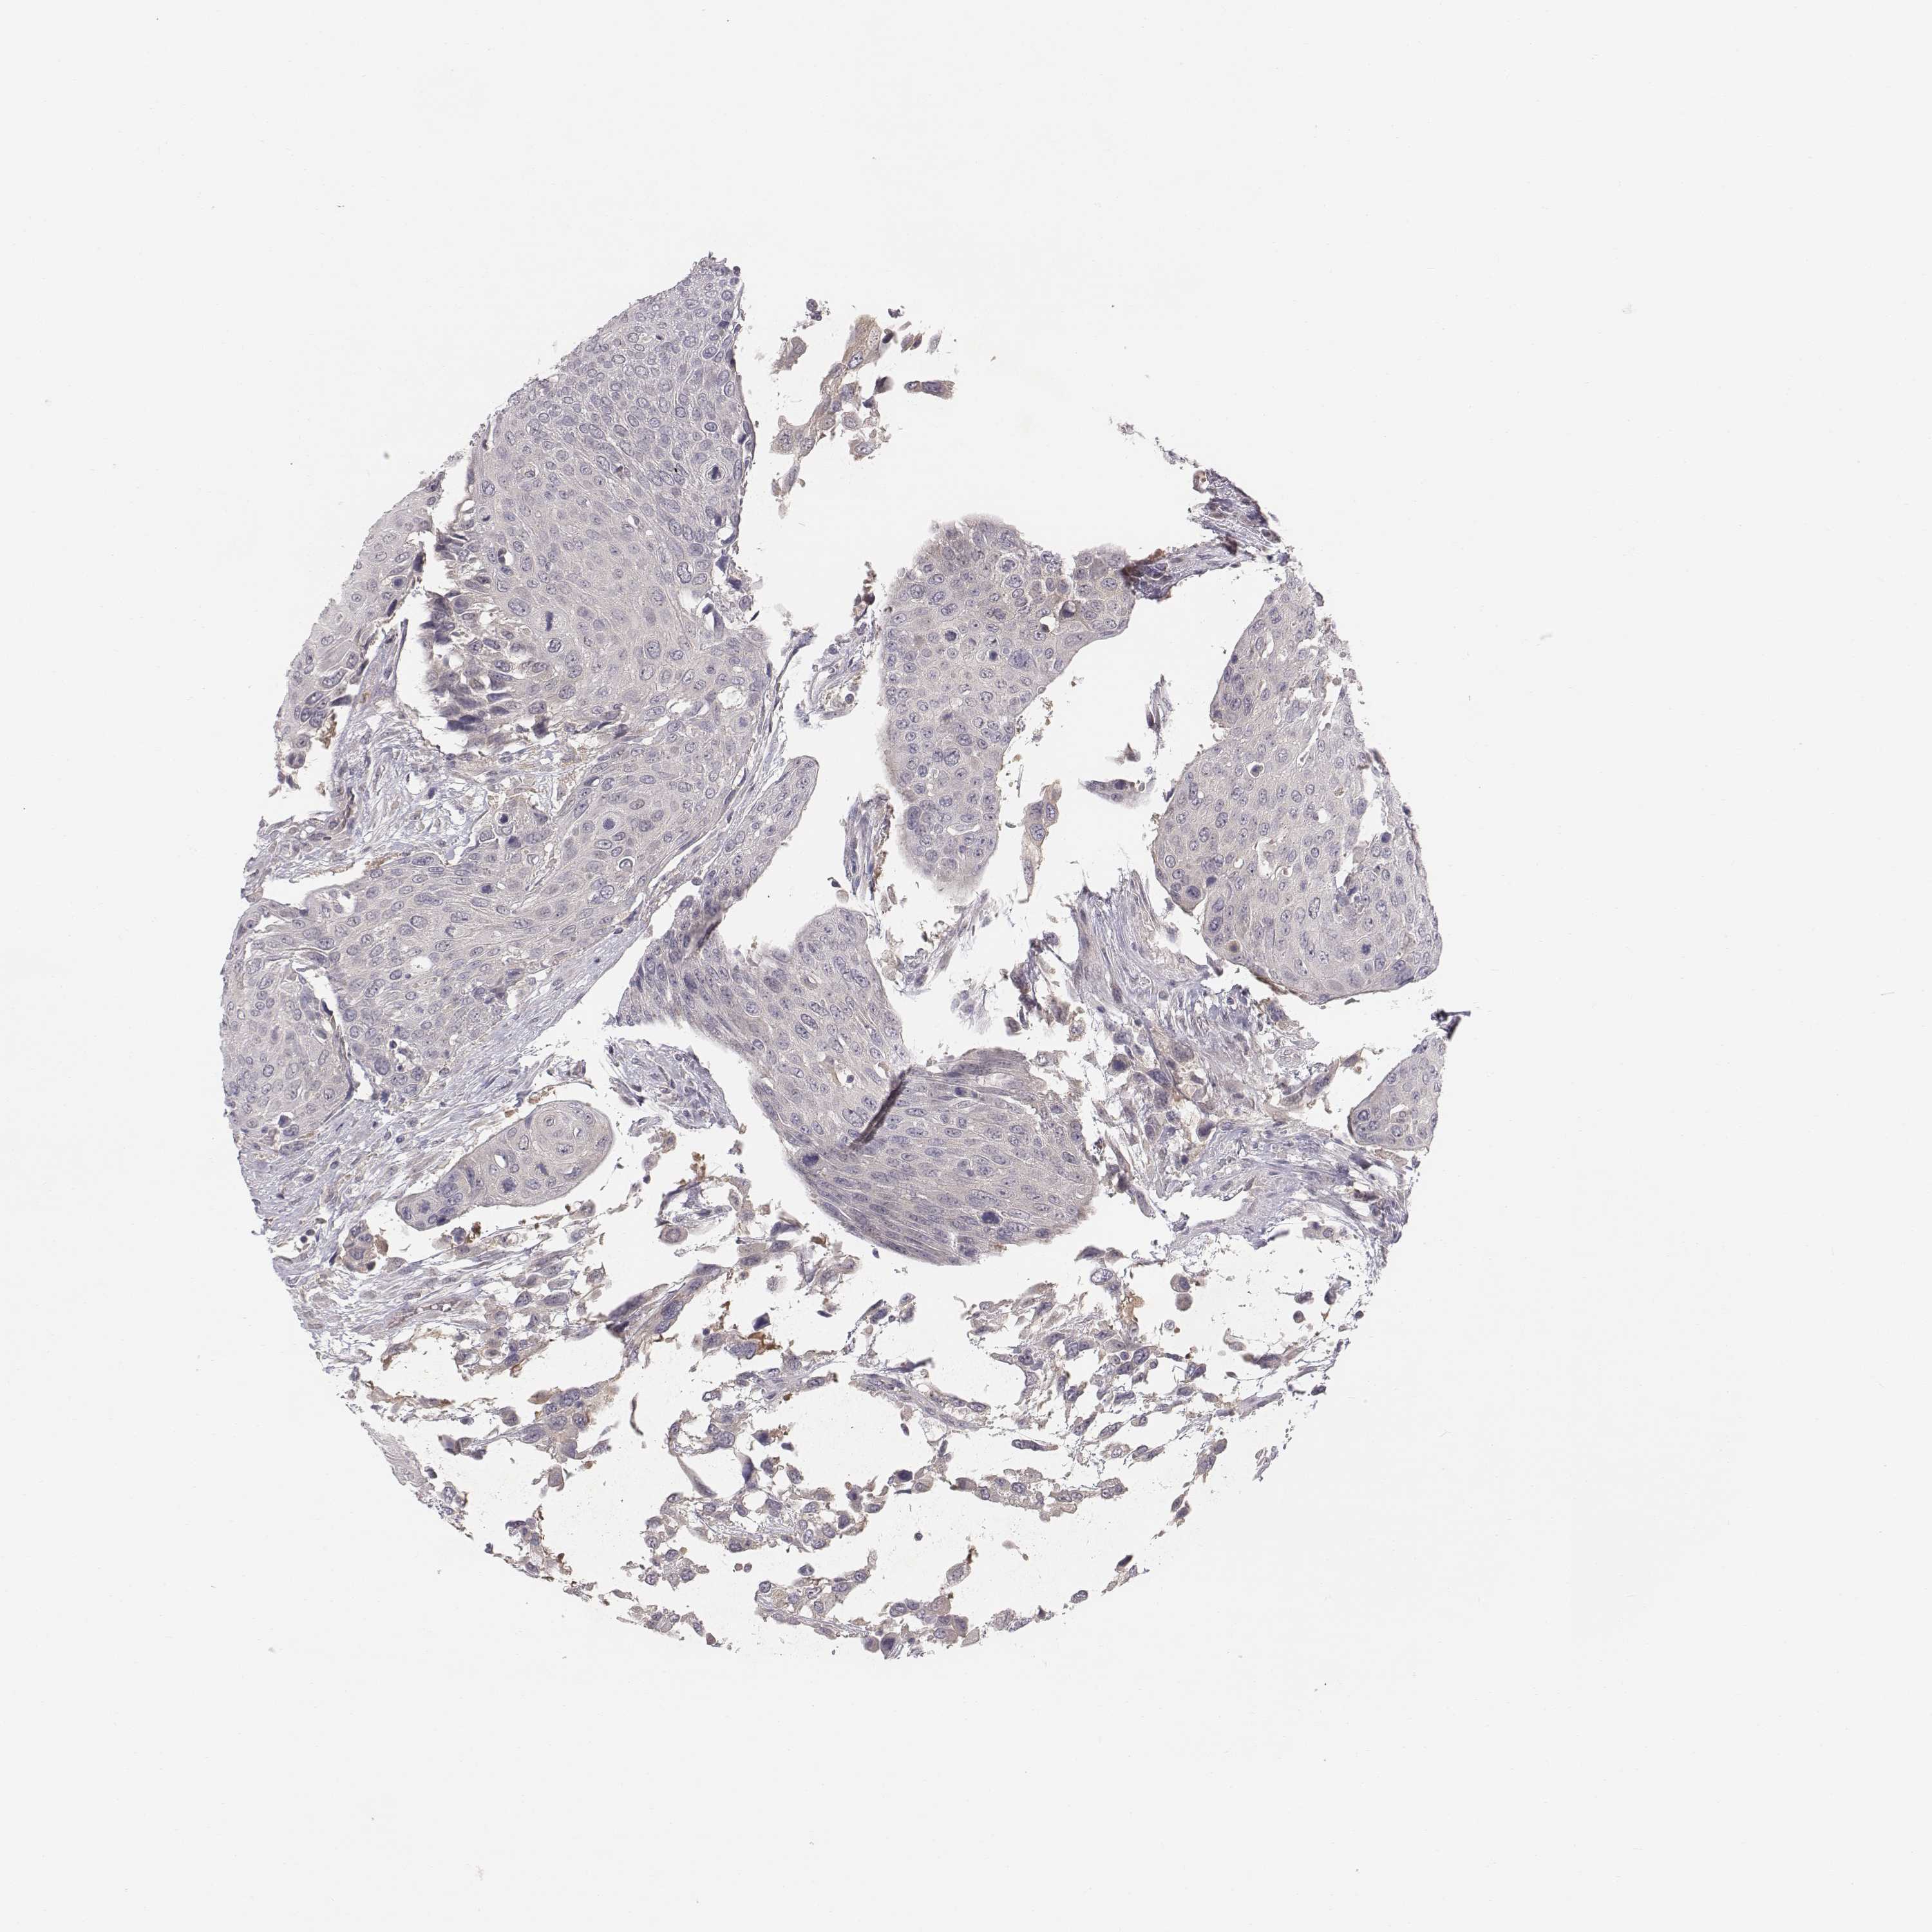

UROTHELIAL CANCER - Protein expressioni

A mouse-over function shows sample information and annotation data. Click on an image to view it in a full screen mode. Samples can be filtered based on level of antibody staining by selecting one or several of the following categories: high, medium, low and not detected. The assay and annotation is described here.

Note that samples used for immunohistochemistry by the Human Protein Atlas do not correspond to samples in the TCGA dataset.

Antibody stainingi

Antibody staining in the annotated cell types in the current human tissue is reported as not detected, low, medium, or high, based on conventional immunohistochemistry profiling in selected tissues. This score is based on the combination of the staining intensity and fraction of stained cells.

Each image is clickable and will lead to virtual microscopy that enables deeper exploration of all samples and also displays staining intensity scores, fraction scores and subcellular localization as well as patient and tissue information for each sample.

Antibody HPA043261

Antibody HPA043264

Antibody HPA044028

Urothelial carcinoma, High grade

Urothelial carcinoma, NOS

Urothelial carcinoma, Low grade